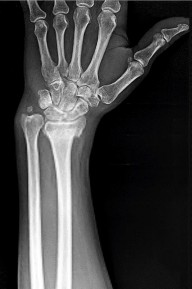

- الأشعة السينية (X-rays): هي الخطوة الأولى في تقييم الكسور، الخلوع، وتغيرات التهاب المفاصل. تساعد في تحديد مدى تدهور العظام والمسافات المفصلية. على سبيل المثال، تُظهر صور الأشعة السينية كسور السلاميات

أو كسور قاعدة العظم المشطي الخامس

، بالإضافة إلى علامات مثل "الدمعة الشعاعية" (Radiographic Teardrop) في الرسغ التي تمثل الزاوية الزندية الراحية الحرجة للكعبرة البعيدة

. - الأشعة المقطعية (CT Scan): توفر صوراً تفصيلية ثلاثية الأبعاد للعظام، وهي مفيدة جداً لتقييم الكسور المعقدة، مثل كسور العظم الخطافي (Hamate Hook Fracture) التي قد لا تظهر في الأشعة السينية العادية